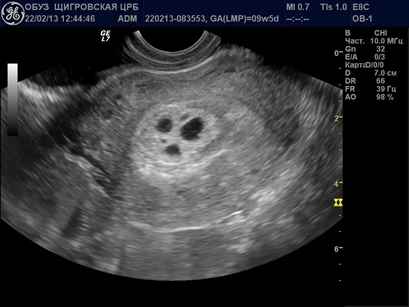

Диагностика с помощью УЗИ: Одним из основных методов диагностики пузырчатого заноса является ультразвуковое исследование. На УЗИ можно увидеть характерные “пузырьки” в матке, которые представляют собой скопления аномальных тканей. Это позволяет врачам быстро и точно определить наличие заболевания.

Для исследования пузырчатого заноса применяются анализы крови, вагинальное обследование и УЗИ. Благодаря современным технологиям, с помощью ультразвука можно легко определить наличие такого заболевания. После проведения операции и лечения, врачи наблюдают за состоянием женщины и проводят разные обследования.

Чтобы увидеть, как выглядит пузырчатый занос, можно посмотреть фото в интернете. Обычно на ультразвуковом исследовании четко видны пузыри, которые располагаются внутри матки. Как можно понять, при таких изменениях в органе, развитие здорового плода не может происходить.

Когда на УЗИ можно увидеть пузырный занос?

Виды пузырного заноса. Выявляется чаще такая патология на сроках 10-12 недель гестации. Содержит такой пузырный занос диплоидное количество хромосом 46 ХХ. При этом стоит сказать, что все хромосомы являются отцовскими. Может быть и кариотип 46 ХУ, однако Х и У также являются отцовскими.